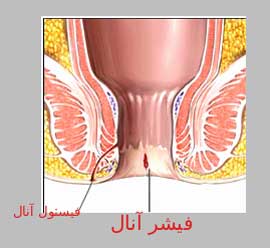

بیشتر بخوانید »بواسیر و شقاق چیست؟

شقاق چیست از شایع ترین عللی که بیماران ، به نام بواسیر مراجعه می نمایند همان: 1- شقاق یا فیشر و 2- بواسیر داخلی میباشد: 1- شقاق یا فیشر (سوزش و درد و ..): شقاق چیست؟ شقاق نام عربی و فیشر نام انگلیسی آن و ترک یا چاک خوردگی نام فارسی آن میباشد که در واقع همان زخم شدن لبه داخلی مقعد …